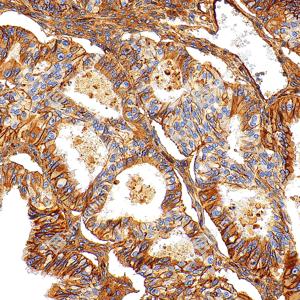

| IHC检测Integrin beta 1/CD29蛋白(货号 GB155629). 样品: 人肝癌, 4%多聚甲醛 (货号G1101) 固定12-24小时. 抗原修复: Tris-EDTA抗原修复液(pH 9.0) (G1203), 100℃, 25分钟. —抗: 1: 3000稀释, 4℃ 孵育过夜. 二抗: S-vision免疫组化多聚二抗(山羊抗兔),即用型 (货号G1302), 室温孵育20分钟. |